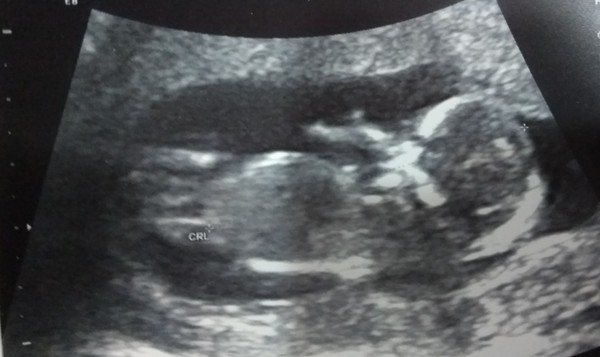

Had my "12 week" scan yesterday, due end of June, but will be having ELCS in early June as it's identical twins! I've known for a few weeks but it's still quite a shock!!

We had our scan yesterday too, all looking good and measuring bang on, I'm 13 weeks today so they confirmed my due date of 21st June. There was so so much information to take in! Our wee one was wriggling about loads, was so exciting to see ☺️

Ah lovely seeing everyone's scan pictures! And 2 ladies having twins - fab!